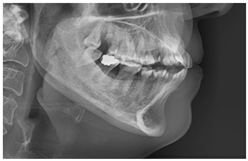

3.2. Dataset Description

3.3. Results Obtained from 2D Lateral Cephalogram Analysis Applying AI Techniques